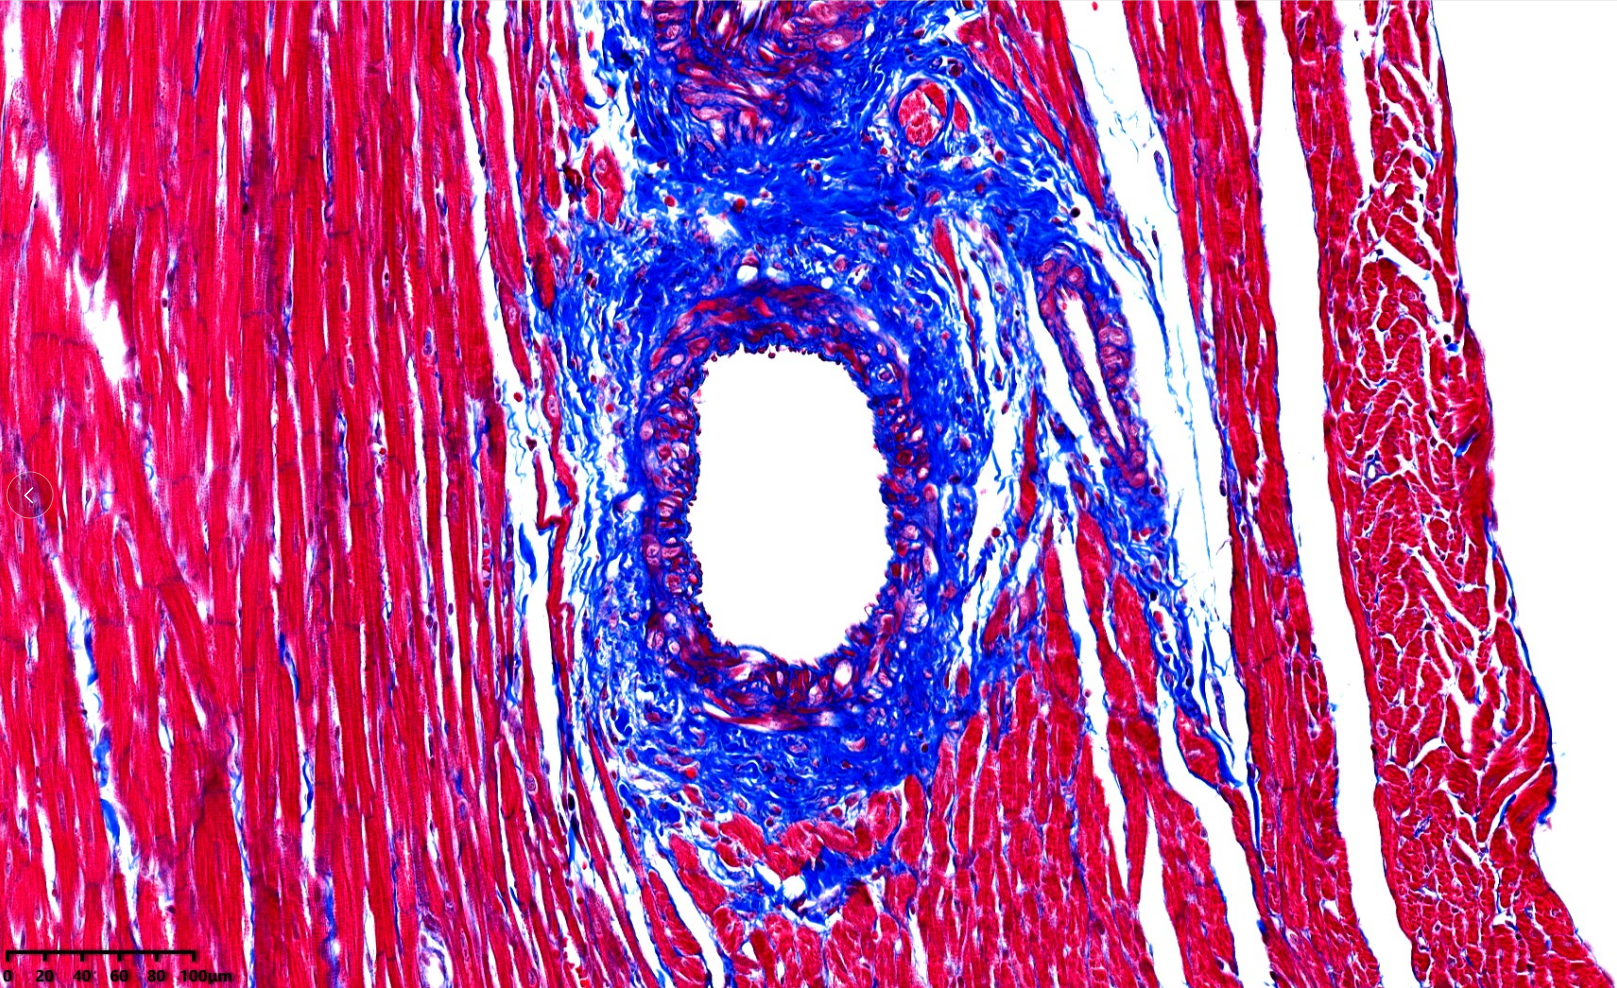

心脏组织病理

病理切片